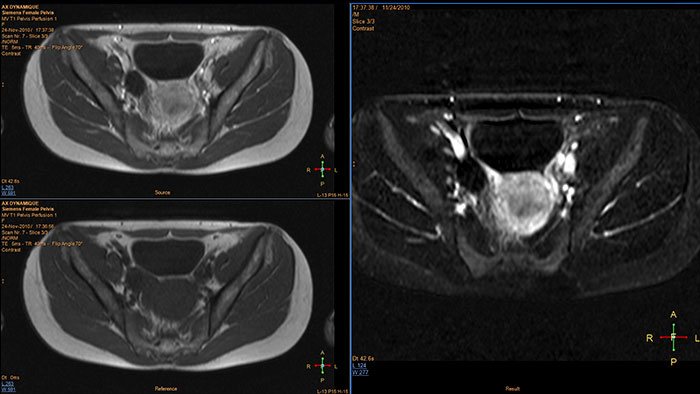

Lesion characterization by reviewing vascular leakage

Designed to visualize T1 weighted DCE 3D datasets and assist in analyzing the tissue response.